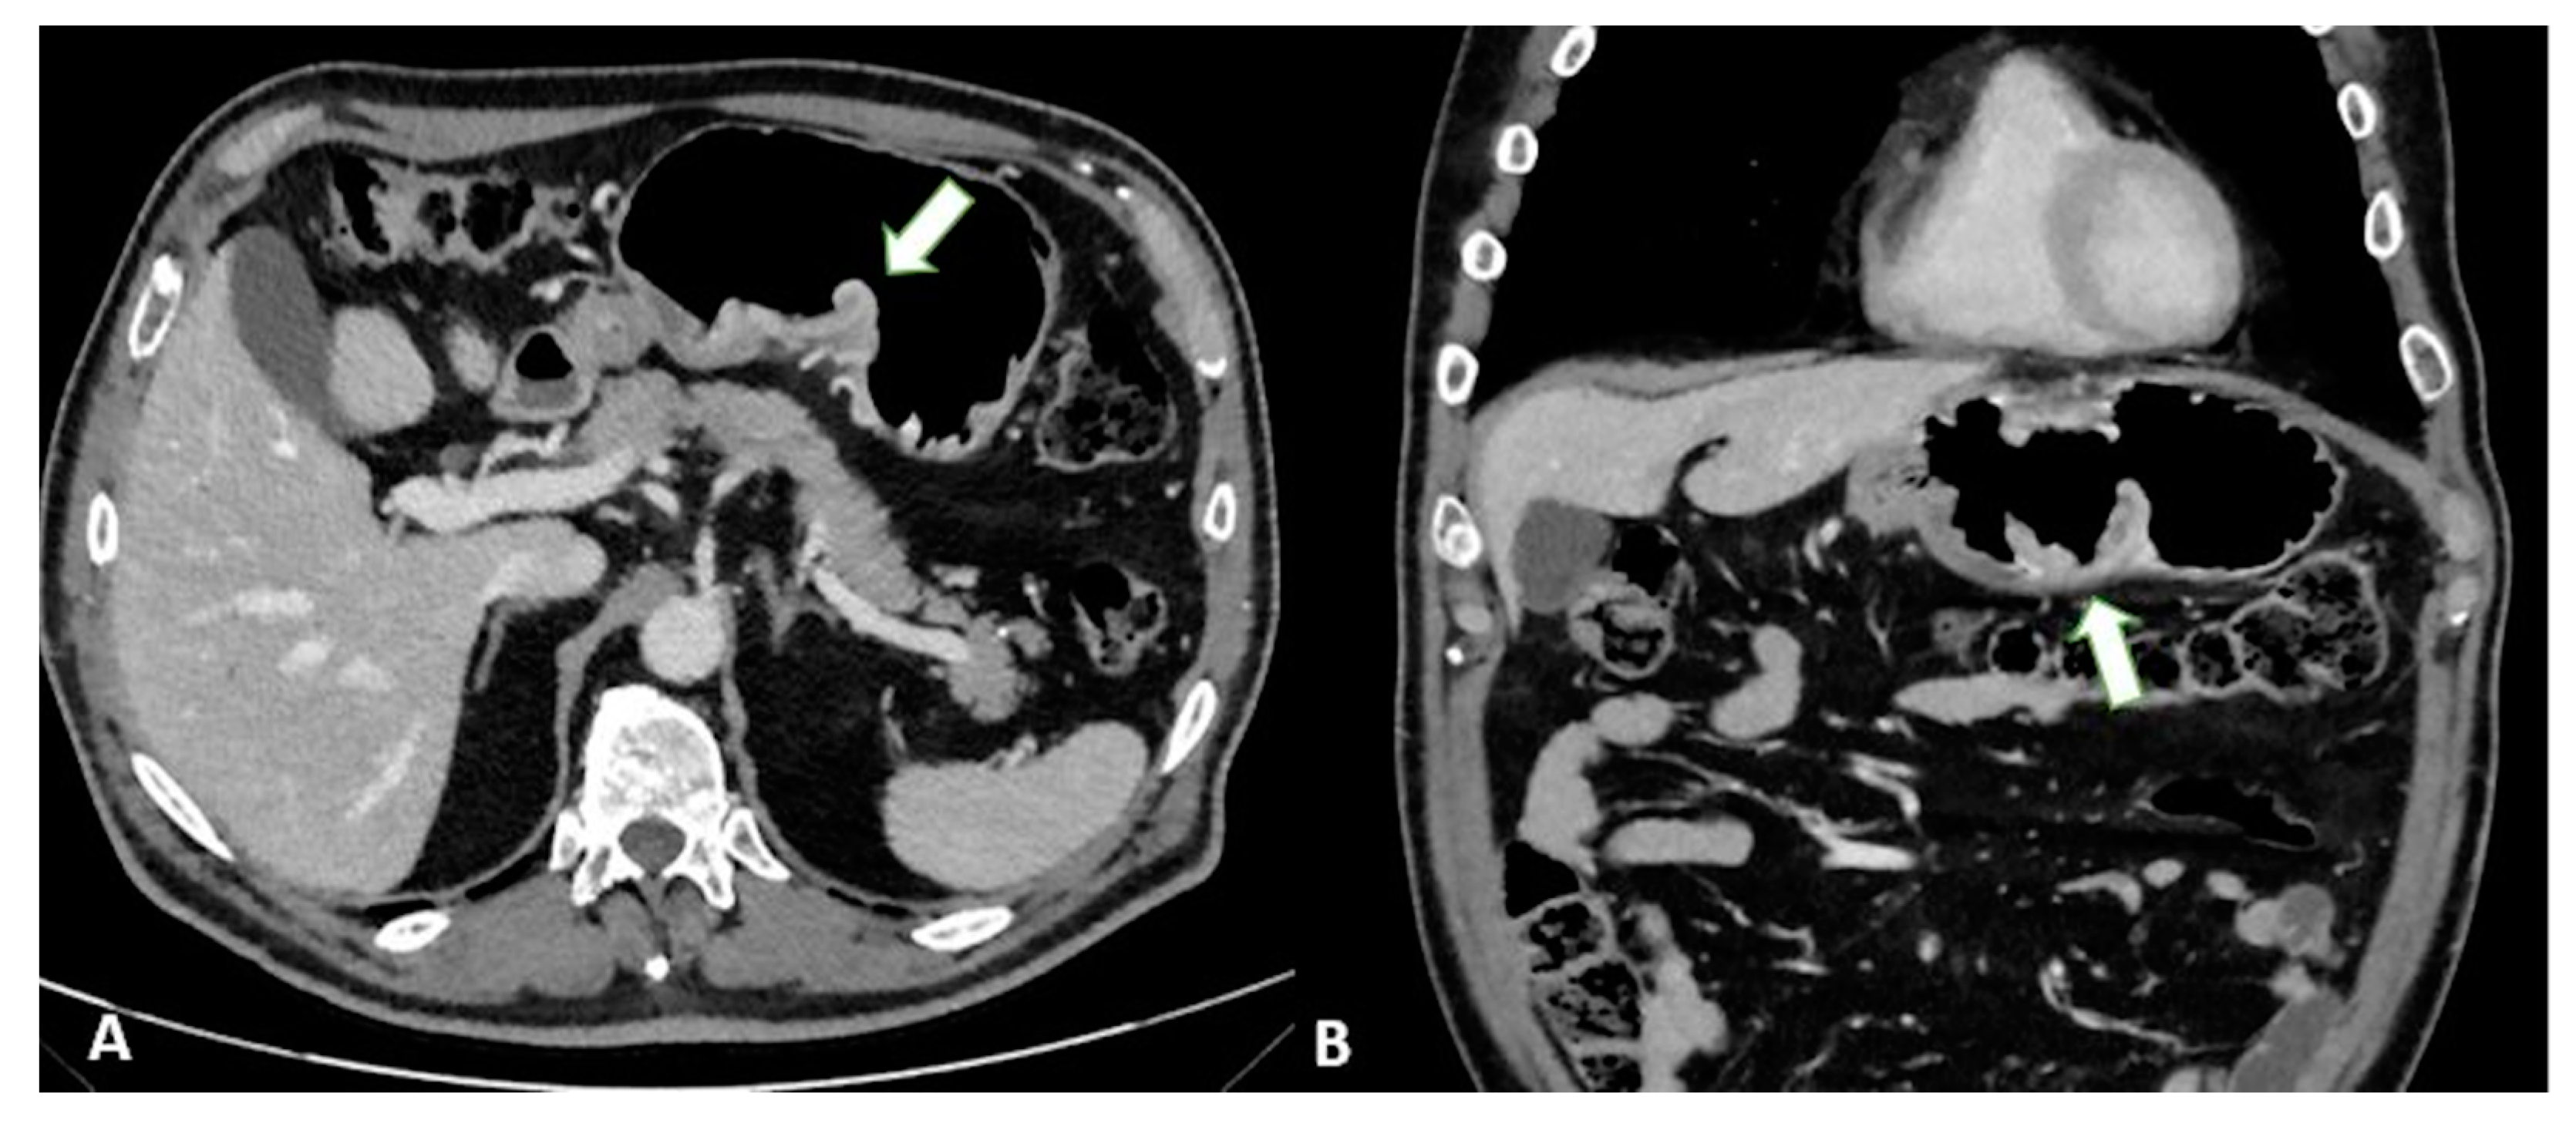

T1a tumors are usually not visible, whereas T1b tumors show mucosal thickening and enhancement. The distinction between T1b and T2 can be made based on the appearance of the thickening base: T1b shows a faint attenuated stripe indicating the submucosal layer, whereas T2 shows a loss of this layer due to the involvement of the submucosa [24] (Figure 1).

Figure 1.

T2 gastric cancer in a 67-year-old-female patient. (A) Axial 2D image in the portal venous phase showing enhanced wall thickening in the lesser curvature side of the low body of the stomach (white arrow). T2 gastric cancer in a 66-year-old-male patient. (B) Axial 2D image (C) Coronal 2D image and (D) Sagittal 2D image showing enhanced wall thickening (white arrow) in the lesser curvature side of the middle body of the stomach. In both the patients, the tumor invades the muscularis propria layer.

T3 tumors have a subserosal invasion, and discrimination between a gastric mass and the outer layer can be difficult: small linear strandings in the gastric fat, due to a desmoplastic reaction, can be confused with serosal involvement (Figure 2 and Figure 3).

Figure 2.

T3 gastric cancer in a 72-year-old male patient. (A) Axial 2D image in the portal venous phase and (B) Coronal 2D reconstruction showing wall thickening (white arrow) in the lesser curvature of the low body of the stomach and inhomogeneous enhancement. The tumor invades the subserosa layer without invasion of the serosa and adjacent structures.